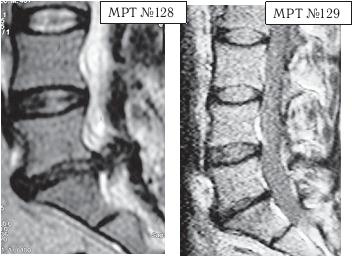

На МРТ № 128 наблюдается состояние поясничного отдела позвоночника после операции: рецидив грыжи межпозвонкового диска в сегменте LV-Sr с отрывом секвестра и его миграции в краниально-дорсальном направлении, разрыв задней продольной связки.

На МРТ № 129 наблюдается состояние поясничного отдела позвоночника после лечения методом вертеброревитологии: отсутствие грыжи межпозвонкового диска в сегменте L — S. В межпозвонковых дисках в сегментах LIV-LV, L — SI наблюдается процесс репаративной регенерации.

Рецидив грыжи межпозвонкового диска после двух хирургических операций — и это у молодого человека в возрасте 16 лет! Чрезмерное увлечение компьютером, малоподвижный образ жизни основательно подорвали его здоровье. Всё это привело к тому, что в течение года, начиная с пятнадцатилетнего возраста, он практически не выходил из больниц. После первой хирургической операции на позвоночнике, менее чем через месяц, боли возобновились. Спустя два месяца его вновь прооперировали по поводу рецидива — грыжи межпозвонкового диска. После второй хирургической операции боли наблюдались практически два месяца подряд, потом затихли, но полностью так и не прошли. Через пять месяцев появилась слабость в обеих ногах. Сделали снимки МРТ, диагностировали рецидив грыжи межпозвонкового диска, естественно рекомендовали сделать очередную третью хирургическую операцию. В промежутках между операциями молодой пациент несколько раз находился на стационарном лечении в неврологическом отделении городской больницы. Именно там, после того как у парня была диагностирована очередная грыжа, лечащий врач посоветовал не спешить с третьей операцией и порекомендовал ему обратиться ко мне в клинику. Конечно, этот случай был далеко не простым и пришлось основательно потрудиться как мне, так и самому пациенту над восстановлением его здоровья. Но зато результат порадовал всех тех, кто непосредственно участвовал в этом процессе, и кто косвенно ему способствовал. Можно сказать, ещё одна судьба была изменена и молодой человек спасён от инвалидной коляски.